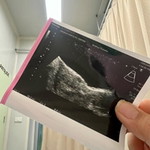

รอมา 3 ปี ICSI ครั้งแรก น้องมาแล้ว ❤️

ได้กลับมาเป็นสมาชิกอีกครั้งหลังจากน้องหลุดไปเมื่อ 3 ปีที่แล้ว พยามเองจนท้อ เลยตัดสินใจทำ ICSI เมื่อปลายปีที่แล้ว ถึงบลาสต์ 8 ตัว ตรวจโครโมโซมผ่าน 2 ตัว (หญิง 1 ชาย 1) ย้ายลูกสาวมาก่อนเมื่อเดือนมี.ค. ตอนนี้มาอยู่ในพุงได้ 7 วีค 5 วันแล้วค่ะ ดีใจมากๆที่ได้เป็นแม่คนกับเค้าซะที รอมานาน ❤️